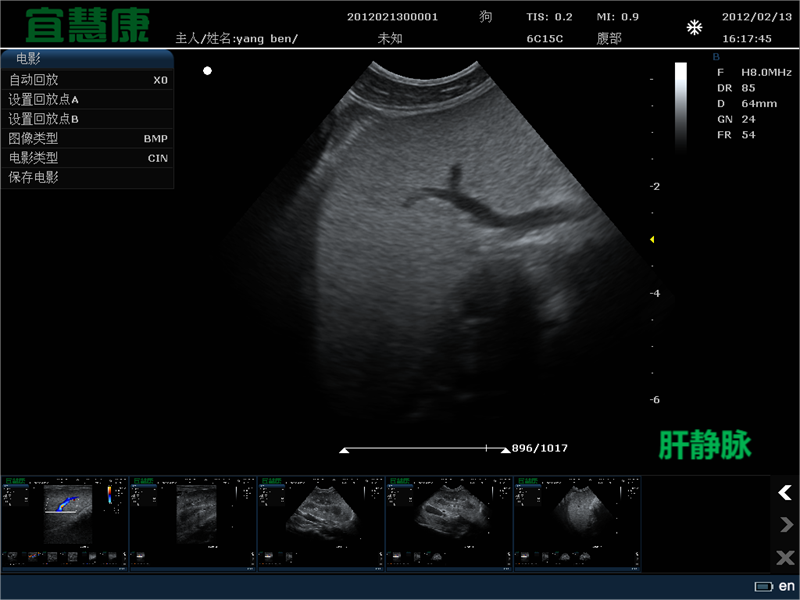

胸部的基本超声检查能够识别伪影,如:肺胸膜线、A线和B线。肺胸膜线是一条水平的高回声线,随着通气前后移动,可见于肋骨线以下。a线是肺胸膜线的人工复制,以明亮的水平线显示在胸膜深处。它们主要在正常的通气肺中可见。相反,在间质-肺泡水肿中可以看到B线(也称为超声肺火箭)。

它们是由超声波束在空气和液体之间的多次前后移动产生的,产生一个长的、垂直的强回声伪影,从胸膜线开始并向下延伸到屏幕,与呼吸同步地沿着胸膜线移动4].它们的出现是由于空气包围的肺组织中积聚了少量液体,产生了高阻抗梯度。它们的数量和宽度与病理的强度相关。